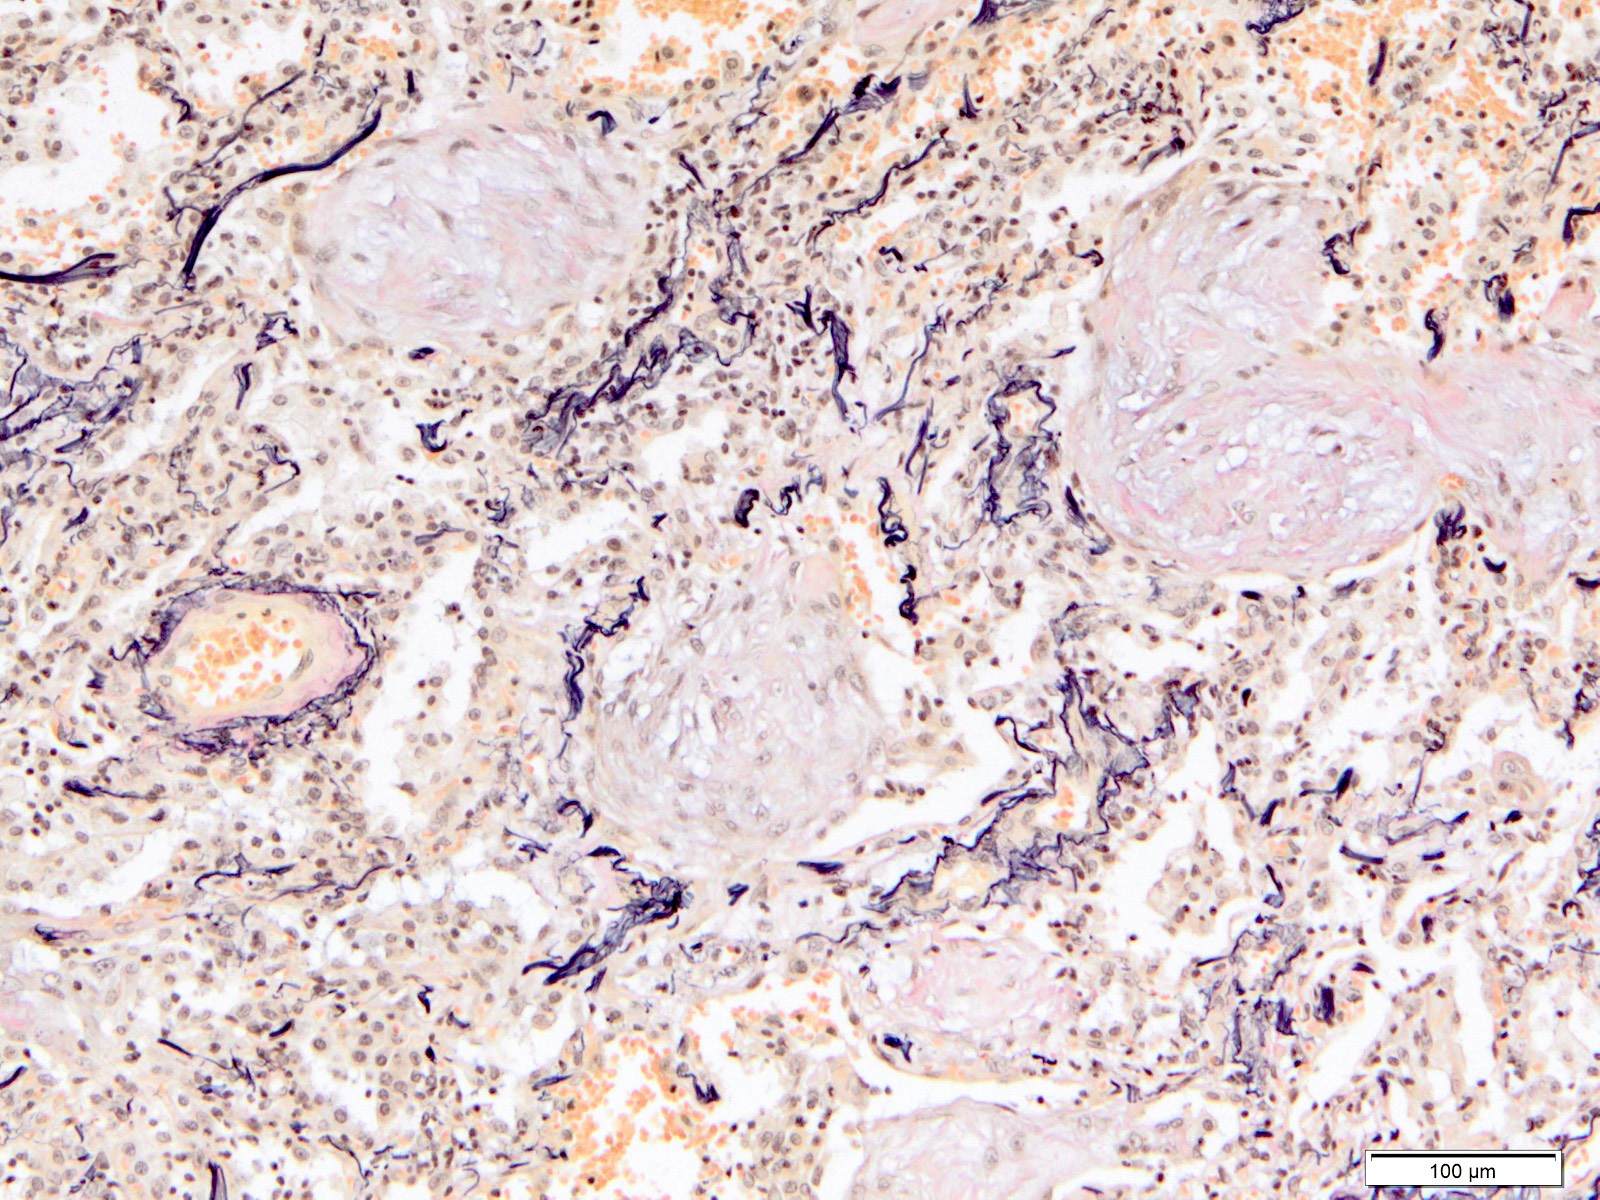

Microscopic (histologic) images

Contributed by Akira Yoshikawa, M.D. and Yale Rosen, M.D.

Positive stains

- Fiber staining (e.g. elastica van Gieson) is helpful to evaluate fibrosis and to evaluate the destruction of the alveolar architecture

- Giemsa, Grocott and Ziehl-Neelsen stains are helpful to identify pathogens

- Immunohistochemistry (not of practical utility):

- Cytokeratin highlights collapsed alveoli and lung architecture